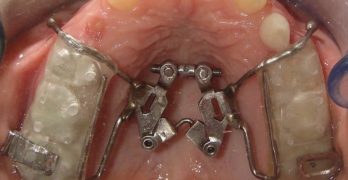

Modulación del crecimiento con aparatos de expansión maxilar

Ya teníamos un rato de no tratar el tema de ortopedia maxilar, así que hoy para todos uds traemos un artículo de nombre Growth modulation with maxillary expansion appliances- A review publicado en el Indian Journal of Orthodontics and Dentofacial Research. Este artículo es una revisión la cual explica varios métodos para expandir el maxilar … Sigue leyendo Modulación del crecimiento con aparatos de expansión maxilar